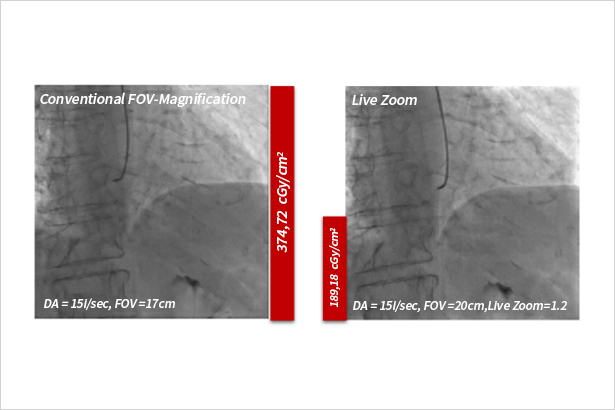

针对动态透视图像进行放大显示,且不会造成剂量增高